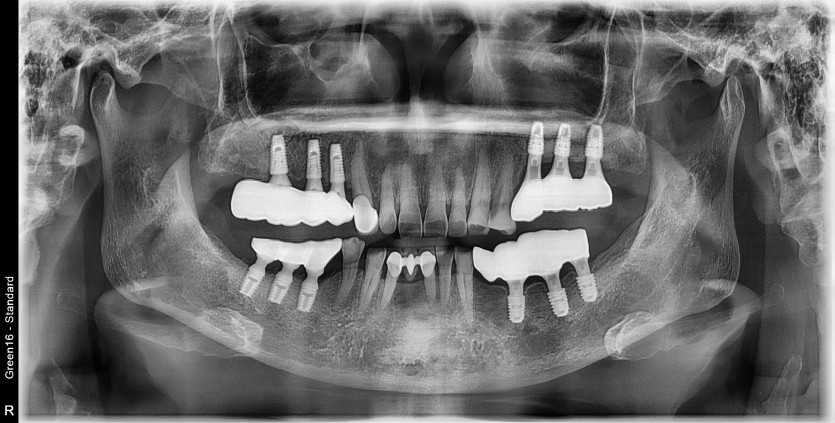

#25.26.27 타원 임플란트 제거 후

임플란트 재식립+치조골 이식술 시행하였습니다.